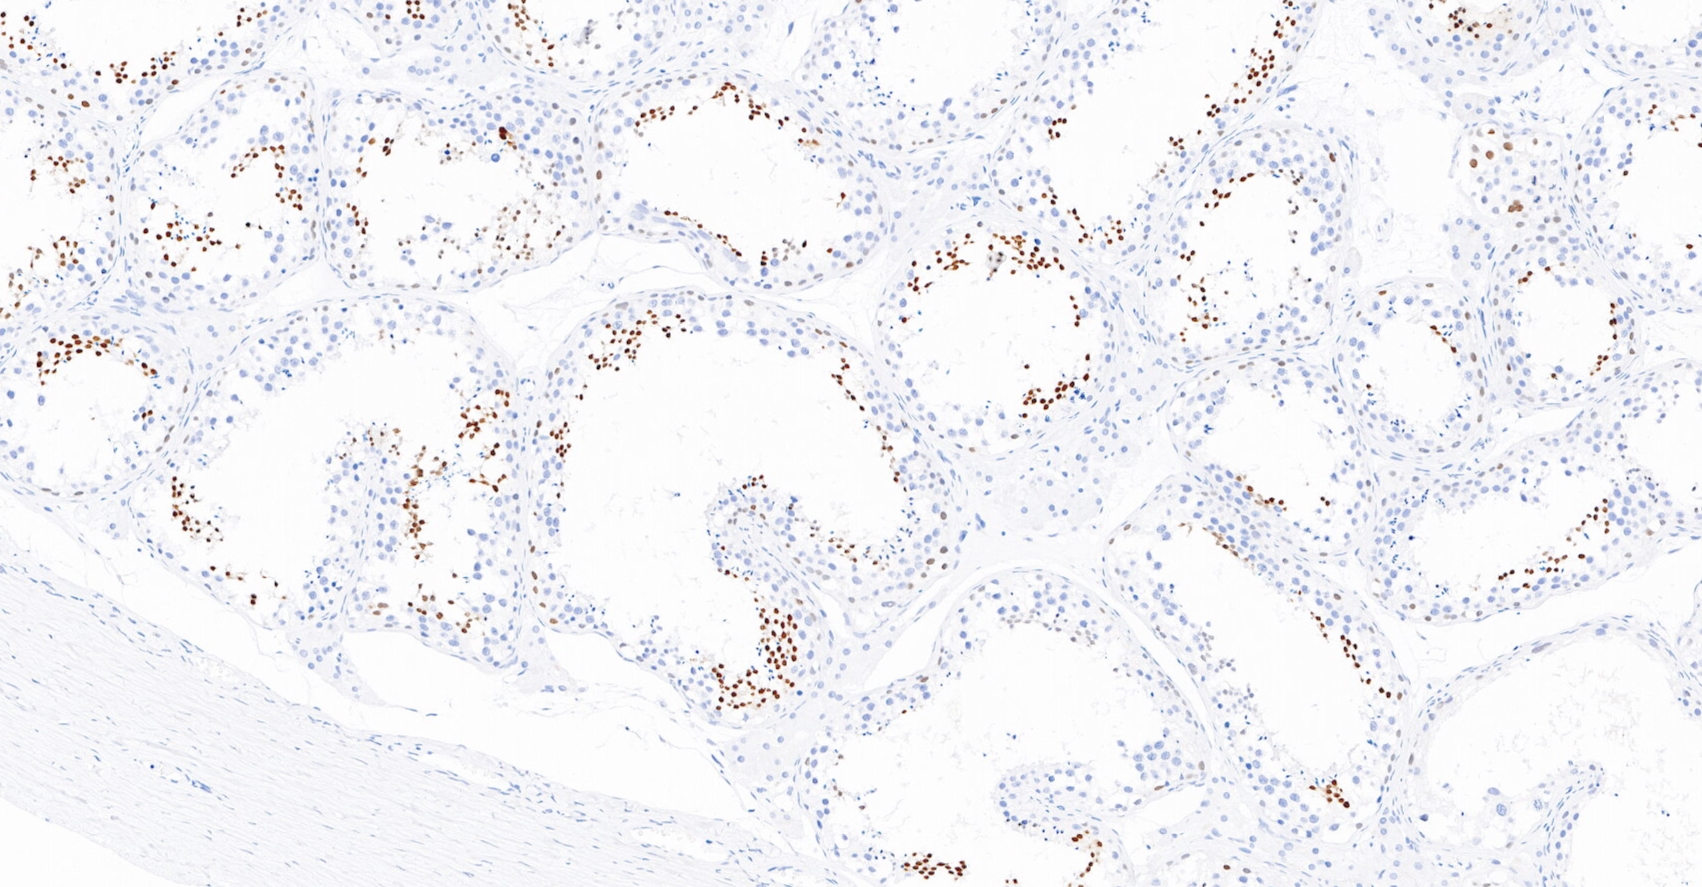

NUT為睪丸核蛋白,基因位于15q14,正常表達于睪丸和卵巢的生殖細胞。NUT中線癌是一種侵襲性腫瘤,伴有NUT基因相關性易位。因此,該抗體在NUT中線癌中有超過90%的核呈斑點狀染色,主要用于NUT中線癌的診斷與鑒別診斷。

睪丸癌石蠟組織,用NUT染色,DAB顯色